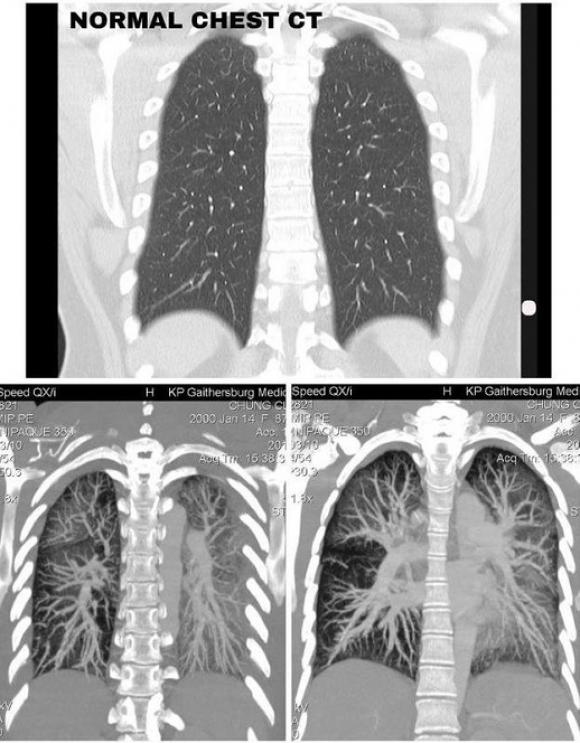

Hình ảnh CT cho thấy phổi Claire tổn thương nặng nề, các mô bị hủy hoại hoàn toàn, ống phế quản có biểu hiện viêm nghiêm trọng.

“Kết quả chụp CT phổi, vô cùng đáng lo. Phổi của người khỏe mạnh khi chụp CT sẽ có màu đen, còn tôi, ở tuổi 19, cả hai phổi toàn màu trắng đục”, Claire nói.

Phổi của người bình thường (trên) và phổi của Claire Chung (dưới). Ảnh: Claire Chung